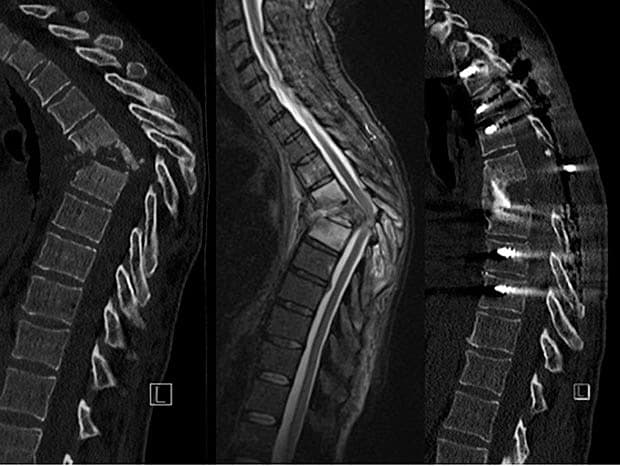

Objektivt sås der gibbusdannelse midttorakalt og god kraft i begge ben, men patienten havde en »gummiagtig« følelse fra papillen og nedefter. En CT af columna thoracalis (A) viste destruktion af Th 5 og Th 6 med et knoglefragment i spinalkanalen. En MR-skanning (B) viste inflammation i Th 4 og Th 7 samt svær kompression af medulla.

Der blev udført en stabiliserende spondylodese, hvor man fjernede resterne af det sammenfaldne corpus. I forbindelse hermed så man pus i operationskaviteten, og en efterfølgende dyrkning viste vækst af Staphylococcus aureus. Patienten blev behandlet med dicloxacillin givet intravenøst og senere peroralt i seks måneder. Ved sidste kontrol et år efter var hun i velbefindende og kunne selv gå.